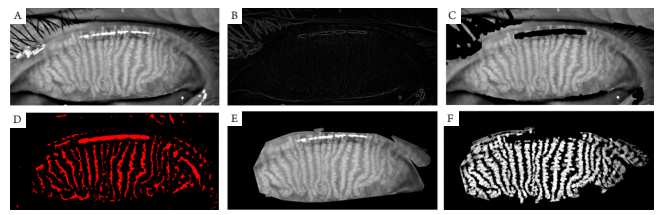

图3 睑板腺图片预处理过程图

Figure 3 The figure of the meibomian gland image preprocessing process

(A)自动截取的睑板腺图像;(B)对眼睫毛和高亮反光点进行边缘检测的效果图;(C)去除眼睑毛和高亮反光点的效果图;(D)Convolution与形态滤波的效果图;(E)去除边缘无效信息的效果原图;(F)为增强睑板腺形态的效果图。

(A) Automatic interception of meibomian gland image; (B) The image of the edge detection on lashes and highlights; (C) The image of the removal the eyelash and the reflective point; (D) The image of the Convolution and Morphological filtering; (E) The effect image of removing invalid edge information; (F) The effect image of enhancing the morphology of meibomian glands.